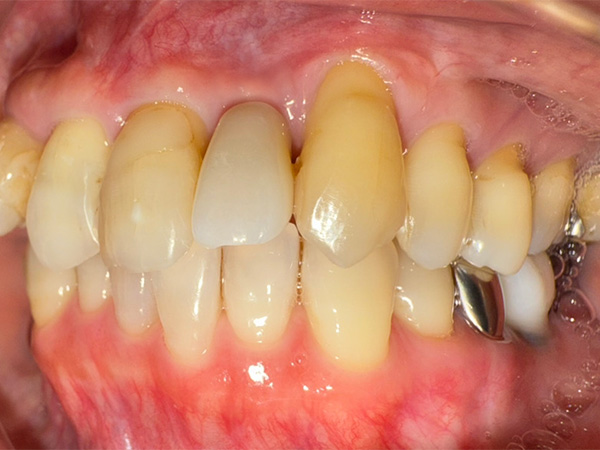

インプラント症例その1

術後